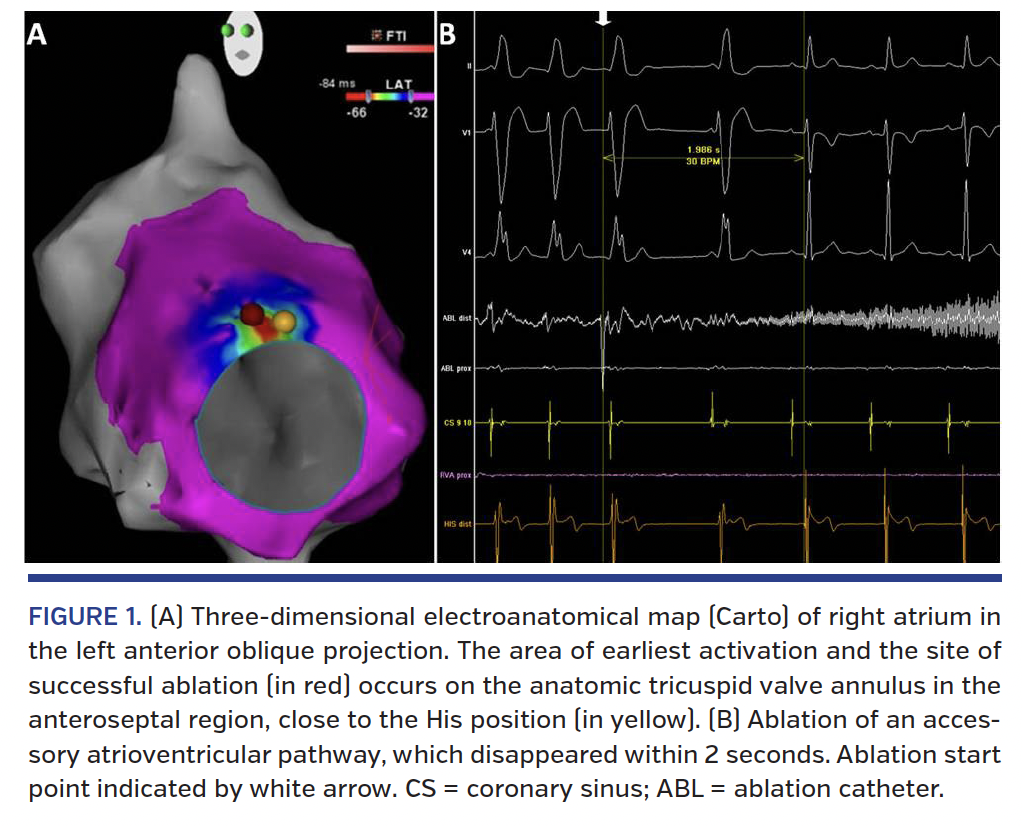

A 39-year-old male patient was referred to our electrophysiology lab with a previously diagnosed anteroseptal accessory pathway with an antegradely conducting effective refractory period of 240 ms. Following diagnostic electrophysiological evaluation, precise Carto electroanatomical activation mapping was performed using a 8 Fr, 4 mm Navistar catheter (Biosense-Webster) from both sides of the interatrial septum, which showed the earliest ventricular activation close to the His position at the right anteroseptal region (Figure 1A). In an attempt to reduce the risk of atrioventricular (AV) block, further mapping was performed using test applications (-30 °C) with a cryoablation catheter (7 Fr, 6 mm Freezor Xtra; Medtronic). As the cryoenergy was applied just slightly anterior to the His position, the accessory pathway disappeared within 2 seconds (Figure 1B), followed by full cryoablation (at -75 °C) for a total period of 4 minutes. The accessory pathway did not appear during a waiting period of 45 minutes and during the clinical follow-up thereafter.

Rapidly conducting accessory pathways at the right anteroseptal position pose a clinical challenge given the associated risk for permanent AV block and the resultant need for lifetime pacemaker therapy. Mapping for the appropriate ablation position is usually performed by conventional means searching for the earliest ventricular activation along the tricuspid annulus and avoiding the regions with the His-potential. Electroanatomical mapping can facilitate the identification of the ideal ablation site by providing a three-dimensional map of the earliest activation site. Combined use of the cryoablation technology with electroanatomical mapping can further increase the precision and safety of the procedure by applying test applications at a lower energy level, which are thought to exert a reversible effect on AV conduction.